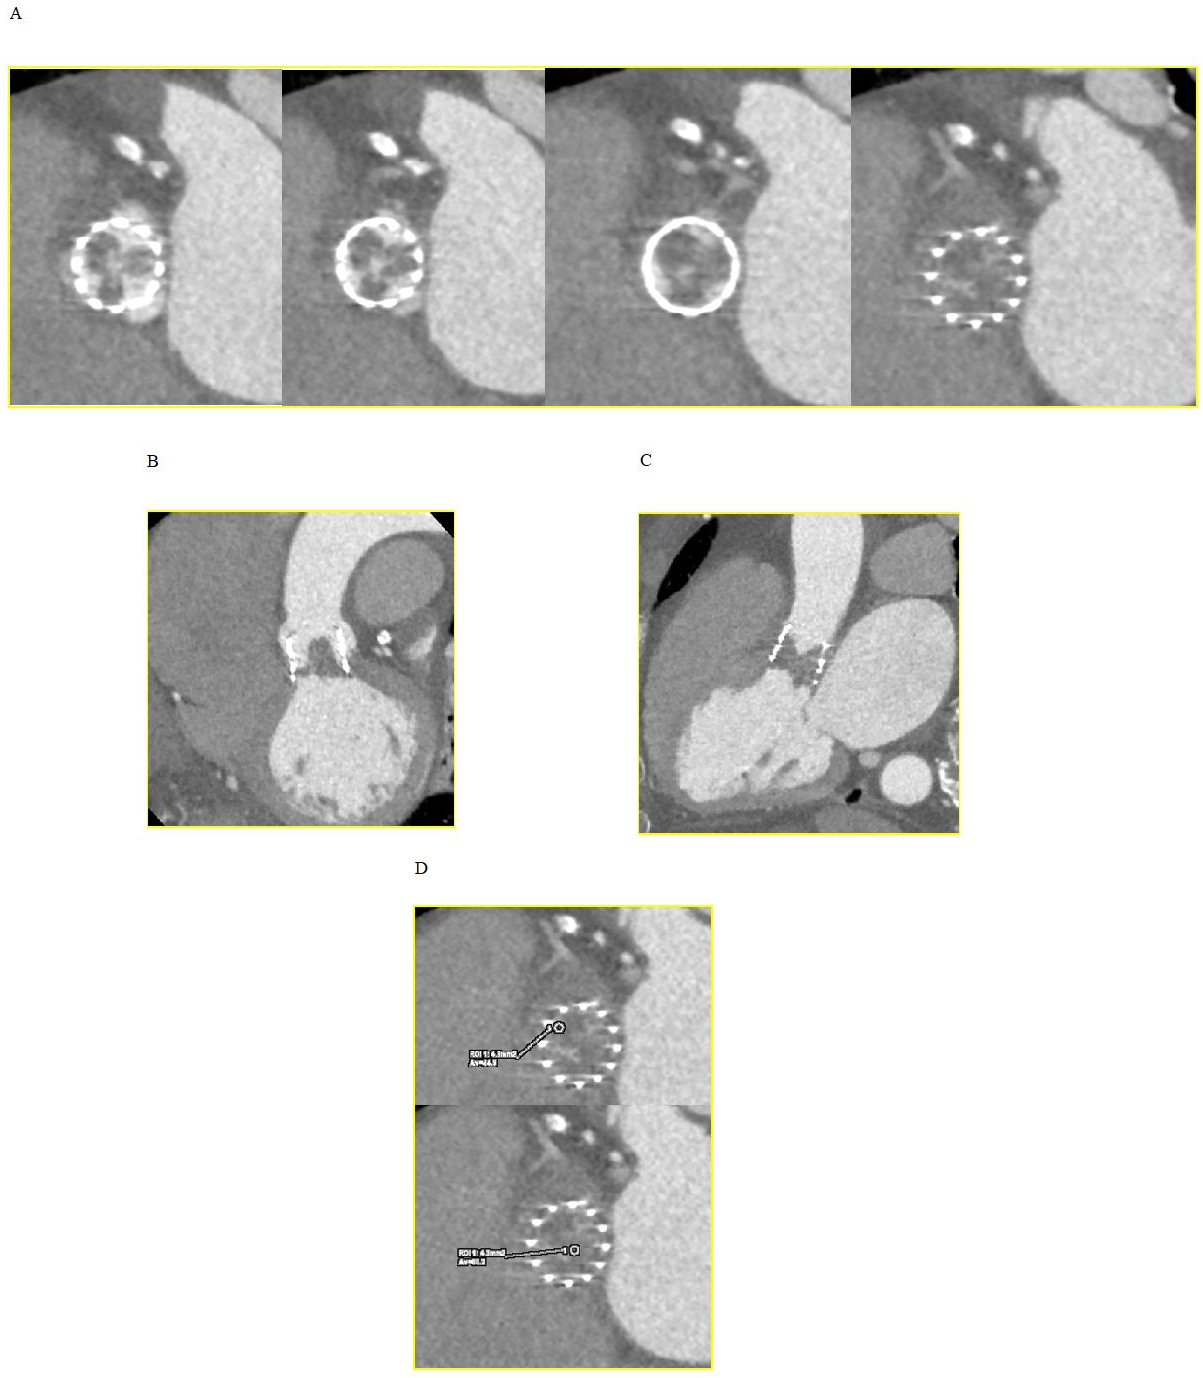

It is believed to be associated with localized thrombogenesis driven by activation of coagulation factors and perturbations in hemodynamics. Hypoattenuating lesions can be observed using multiplanar and three-dimensional (3D) volume-rendered CT reconstructions as 1–5 mm wedge-shaped or semi-lunar hypodense opacities, remaining visible during both systole and diastole (Fig. 2). They are typically located at the periphery and base of the leaflets and may extend to varying degrees to the edges of the leaflet in the center of the bioprosthetic frame, with the potential to result in RLM [29].

Fig. 2.Hypoattenuated lesions at CT. (A) Short axis view of the

transcatheter heart valve showing thickened and hypoattenuating leaflets. (B)

Coronal oblique view. (C) Sagittal oblique view. (D) CT attenuation levels lower

than those observed within the myocardium (